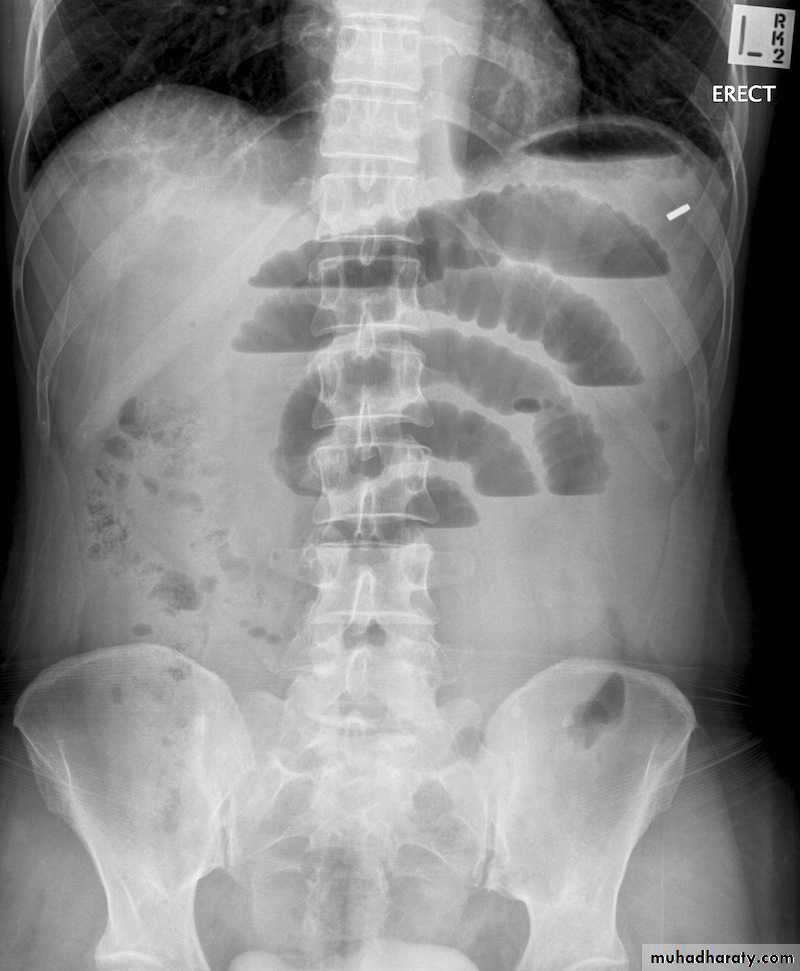

Large bowel obstruction

• Subacute to chronic presentation with abdominal pain and distension and constipation (colorectal carcinoma).

• Acute presentations of LBO may be seen with sigmoid volvulus, cecal volvulus and diverticulitis.

Signs of large bowel obstruction on AXR:

• Dilated large bowel loops, which have the following features

• Peripheral location• Few in number

• Large: above 5.0 cm diameter

• Wide radius of curvature

• Haustra, seen as thick white lines that are widely separated, and may or may not extend right across the bowel (compare these features with those of the small bowel valvulae conniventes described above).

• Contain solid faeces

• Small bowel may also be dilated if the ileocecal valve is ‘incompetent’

• Depending on which large bowel loops are dilated, an approximate level of obstruction may be suggested on AXR.

• With respect to the cause of LBO, AXR appearances are generally non-specific and non-diagnostic.